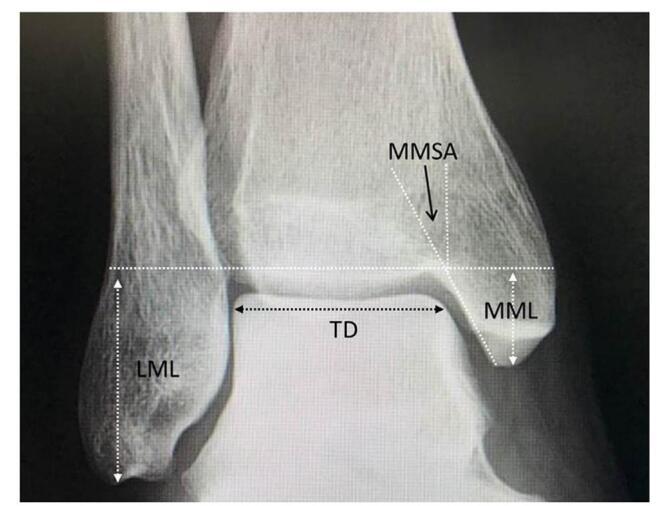

Our systematic review analyzed 26 studies with 8514 participants. Young age was a risk factor in four studies, and female gender in one. High body mass index, increased training hours, competitions, and intense preseason training also raised risk. Anatomical factors included lower calcaneal pitch angle, wider medial malleolar slip angle, higher Talocalcaneal angle, and lower limb varus malalignment. Stress fractures were higher among midfielders in one study, while two others found no positional differences. Additional risks were elevated parathyroid hormone, higher bone-specific alkaline phosphatase, lower 25OH levels, fasting, and perceived stress from negative life events.

我们的系统评价分析了26项研究,涉及8514名参与者。四项研究表明年龄小是一个风险因素,一项研究表明女性是风险因素。高体重指数、训练时间增加、比赛次数和季前强化训练也会增加风险。解剖学因素包括跟骨倾斜角较低、内踝滑动角较宽、距跟角较高以及下肢内翻畸形。一项研究表明中场球员应力性骨折发生率较高,而另外两项研究未发现位置差异。其他风险因素包括甲状旁腺激素升高、骨特异性碱性磷酸酶水平较高、25OH水平较低、禁食以及负面生活事件带来的感知压力。